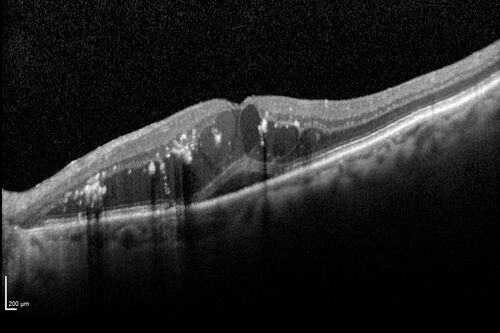

89 year old female with peripapillary CNVM treated with Lucentis. Vision was 20/25 OS 3 weeks ago.  She noticed vision loss OS.  Vision had dropped to 20/60.  She had a fresh MA and was treated with laser.

Retinal Arterial Macroaneurysm treated with Laser